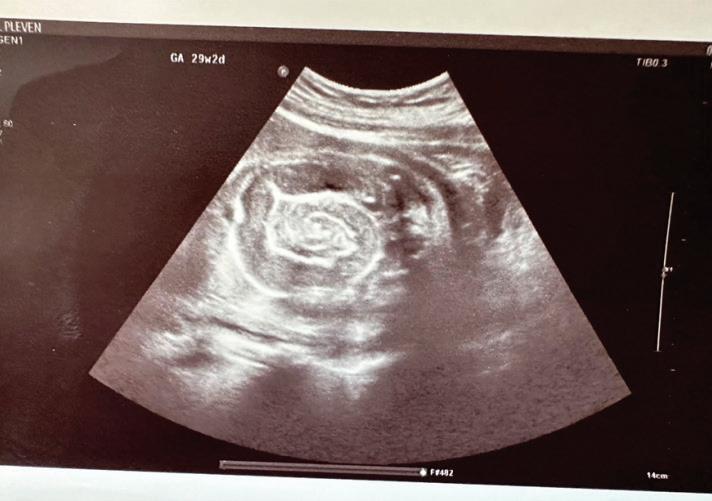

20-годишна бременна жена в 29 ге -

стационна седмица, примигравида, е хоспитализирана в Клиниката

по акушерство и гинекология на УМ -

БАЛ ,,Д-р Георги Странски” – гр. Пле -

вен с преждевременно пукнат око -

лоплоден мехур, високи стойности на артериалното налягане (150/100 mmHg) и изразени отоци по долните крайници. Пациентката е с придружаващо заболяване ЗДТ1, диагностициран в детска възраст, на терапия с бързодействащ инсулинов аналог (Glulisine) и дългодействащ инсули -

нов аналог (Glargine). Анамнестичните данни показват, че пациентката е с

повишено артериално налягане от 20 дни със стойности до 160/100 mmHg,

кифосколиоза, силно раздути дебелочревни бримки, ехопозитивни тънкочревни бримки, единична пъпна артерия, десностранно криво ходило, съмнение за артрогрипоза на големите стави, отговарящи на caudal regression sequence.

Физикалният преглед на бременната показа нормална белодробна функция с везикуларно дишане без добавени хрипова находка и норморитмична, нормофреквентна сърдечна дейност с АН 150/100 mmHg.

околоплодна течност, което затруднява визуализацията на вътрешните органи на плода. Прави впечатление

на същите. Проведе се токолитична терапия, антибиотична

провежданата антихипертензивна терапия.

На третия ден от хоспитализацията мултидисциплинарен екип обсъди по-нататъшното поведение. Взе се решение за родоразрешение чрез Цезарово сечение в интерес на майката поради екстремно незрелия гестационен срок, седалищно пред

персистиращите високи стойности на артериалното налягане и

от УЗИ за малформативен плод.